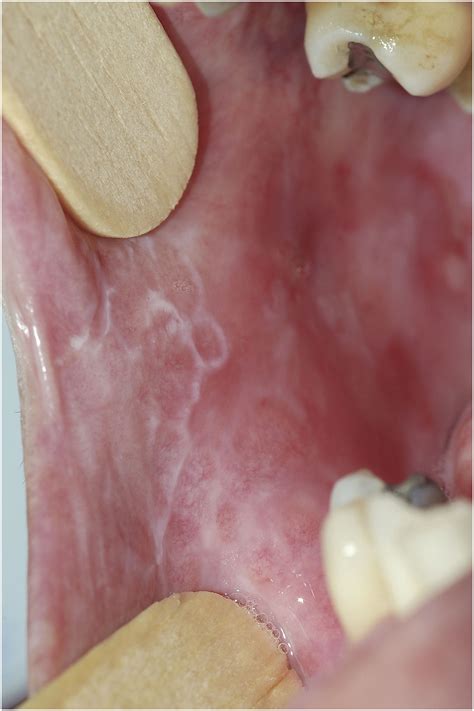

Living with a chronic condition can be challenging, but understanding the nature of your diagnosis is the first step toward effective management and relief. Erosive Lichen Planus is a particularly painful variant of oral lichen planus, a condition that affects the mucosal tissues in your mouth. Unlike the milder reticular form, which often presents as painless white lacy patches, the erosive type is characterized by open sores or ulcers that can significantly impact your daily quality of life, making eating, drinking, and even speaking a difficult task.

At its core, Erosive Lichen Planus is an autoimmune inflammatory condition. While the exact cause remains unknown, it occurs when the body's immune system mistakenly attacks the lining cells of the mucous membranes. This persistent inflammation leads to the breakdown of the tissue, resulting in painful, red, and eroded areas that are often rimmed with white, radiating lines known as Wickham striae. Because it is a chronic condition, patients often experience periods of remission followed by painful flares.

• White striae: Lacy, web-like white lines surrounding the red or ulcerated areas.